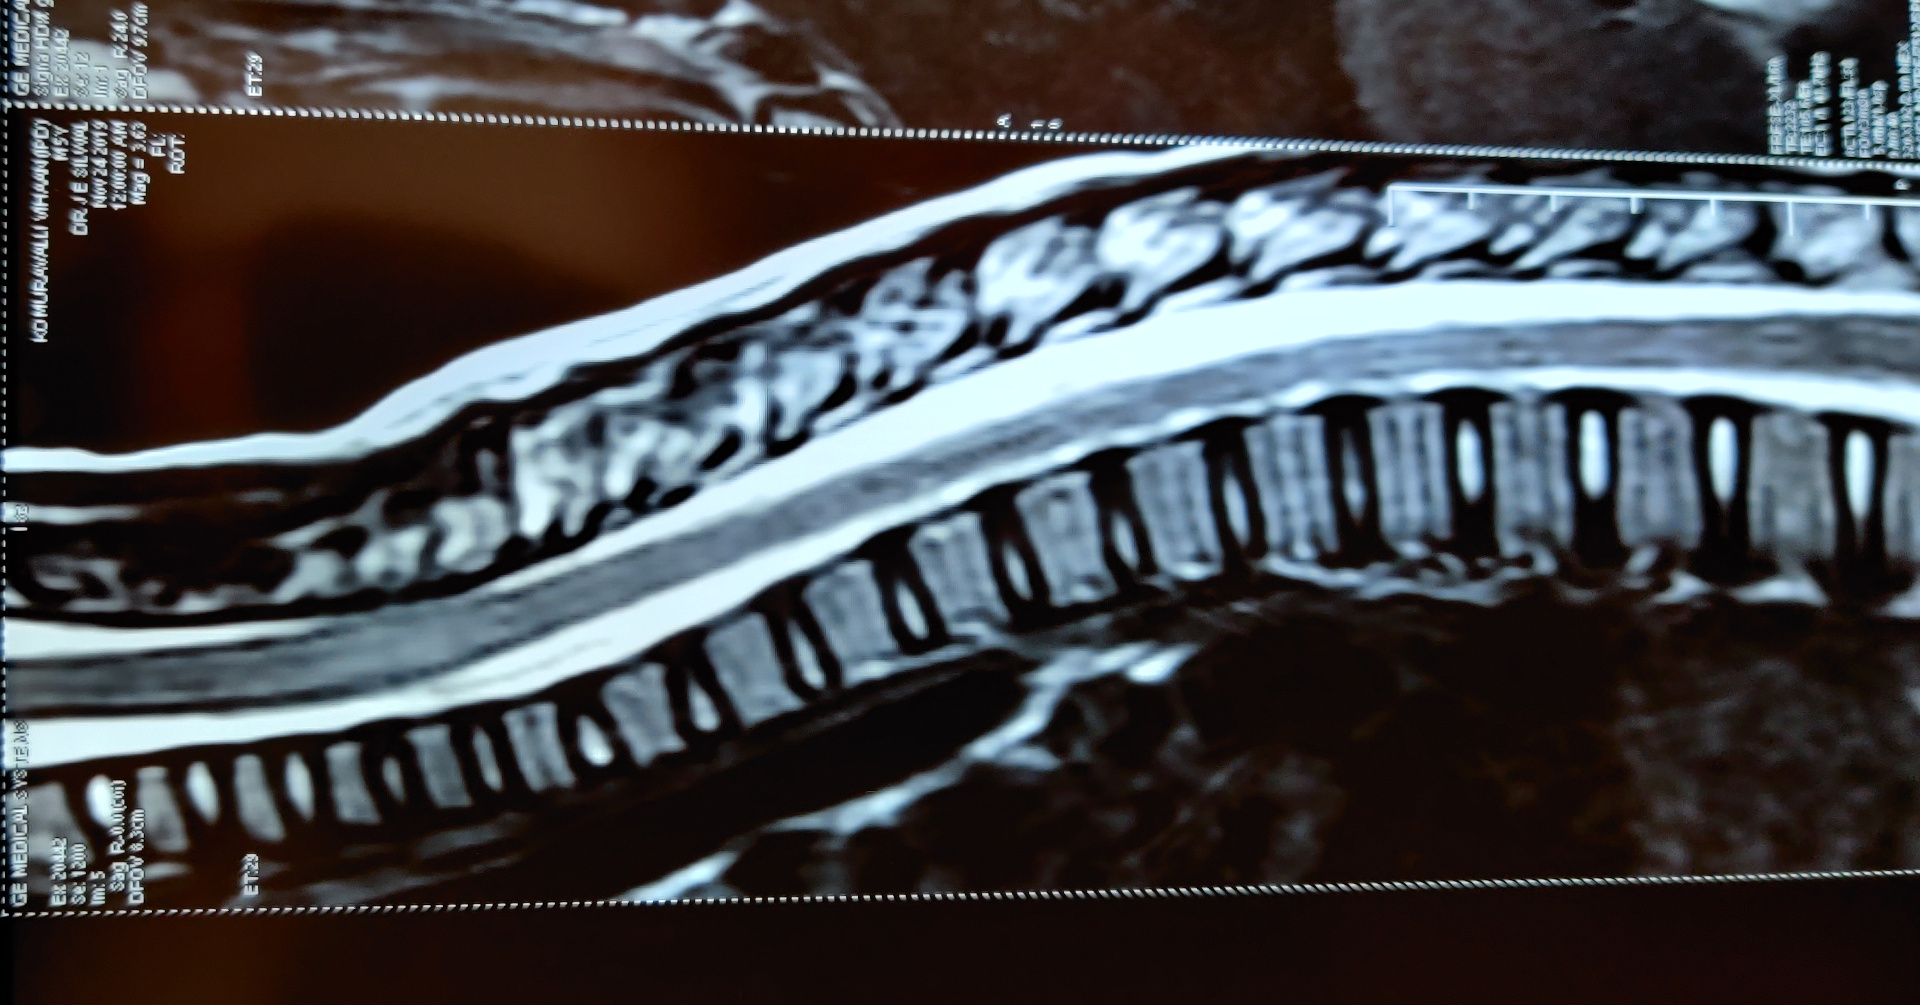

5years old boy with normal development history came with features of altered sensorium and frequent seizures. He went into status epilepticus requiring multiple antiepileptic medications and was ventilated for 7 days. His MRI brain and spine was suggestive of acute disseminated encephalomyelitis(ADEM). The antibodies for NMOSD(NMO and anti-MOG antibodies) were negative.He was treated with injection methylprednisolone and IVIG(immunoglobulin). Now after discharge he has become as normal as before.